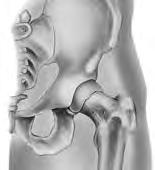

Substituição total da anca

A substituição total da anca (artroplastia da anca) é uma cirurgia executada para substituir a articulação da anca quando a mesma se encontra danificada por desgaste, lesão ou doença. A articulação da anca é uma articulação de "esfera e encaixe", e é a maior articulação do corpo que suporta peso. A parte superior do fémur, que apresenta um formato esférico (osso da coxa) situa-se na cavidade do acetábulo (área oca) do osso pélvico. A união da articulação é assegurada por ligamentos e músculos. A cavidade encontra-se revestida de cartilagem (tecido firme e flexível) que pode ficar danificada ou desgastada, provocando dor. As patologias de artrite, infeção, lesão ou perda de fornecimento de sangue à esfera do fémur podem danificar a articulação. Se tiver dificuldades em caminhar ou em aliviar a dor, poderá estar a precisar de uma cirurgia de substituição da anca.

O cirurgião vai fazer uma incisão (corte) na sua anca. Durante a cirurgia, o cirurgião vai aceder à articulação da anca afastando os músculos e outras estruturas para o lado. As partes danificadas da sua articulação da anca serão removidas com ferramentas especiais. Serão colocados implantes feitos de metal, cerâmica e/ou plástico, para substituir a parte óssea removida. Em seguida, o cirurgião poderá fixar os implantes, utilizando parafusos e cimento ósseo, ou criar um ajuste perfeito, se a qualidade do osso o permitir. Assim que as partes estiverem no sítio, serão unidas, da mesma forma que se encaixa uma esfera numa cavidade, e os músculos e outros tecidos em torno da articulação serão repostos nas suas posições originais. A incisão será fechada com pontos, agrafos ou cola, e será coberta com um penso. A realização desta cirurgia poderá aliviar a sua dor, tornar a articulação da anca mais estável e melhorar o movimento da perna.

Componente de substituição da anca Cabeça

Revestimento

Vista frontal Vista lateral

Pélvis Fémur